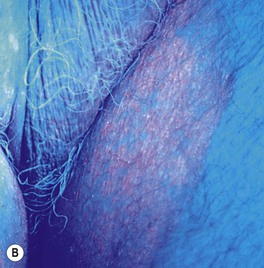

– Intertriginous – thin red-brown plaques in the axillae and groin/upper inner thigh that may be misdiagnosed as tinea cruris (see Table 60.5; Fig. 61.9).

Fig. 61.9 Erythrasma. A Pink to brown scaly patches on the upper inner thighs. B Coral-red fluorescence upon illumination with a Wood's lamp. C Hyperpigmented plaques in the inguinal and periumbilical areas (intertriginous zones). D Well-demarcated, scaly, hyperpigmented plaque of disciform erythrasma. A, B, Courtesy, Louis A. Fragola, MD.

• Bright, coral-red fluorescence with Wood's lamp examination (see Figs. 61.9B and 13.2).